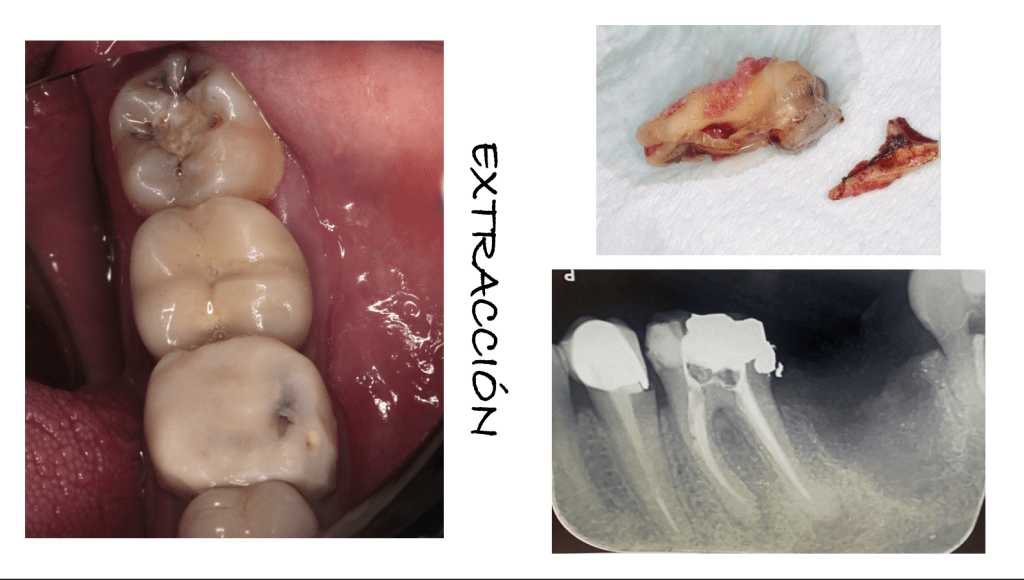

Extrusión quirúrgica